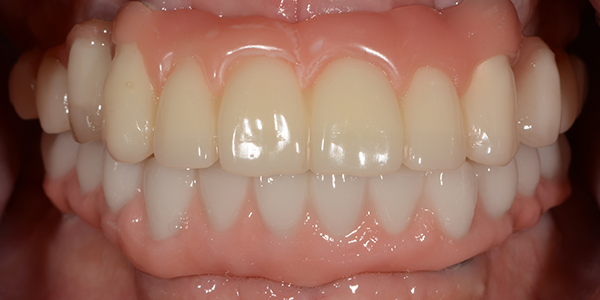

Maxillary Implant-Supported Crown and Bridge – Mandibular Implant-Supported Fixed Complete Denture

After Treatment